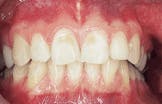

Case 5

Erosion

1. Identify the cause of erosion.

a. bacteria

b. abnormal mechanical forces

c. functional wear

d. acids

e. none of the above

2. Identify the areas likely to exhibit erosion with a lemon-sucking habit.

a. facial surfaces of anterior teeth

b. lingual surfaces of anterior teeth

c. interproximal surfaces of anterior teeth

d. any of the above

3. Identify the areas likely to exhibit erosion with chronic vomiting.

4. Identify the TRUE statement concerning erosion.

a. resembles attrition

b. resembles caries

c. always asymptomatic

d. treated with restorative procedures

CASE 5: 1 = d; 2 = a; 3 = b; 4 = d